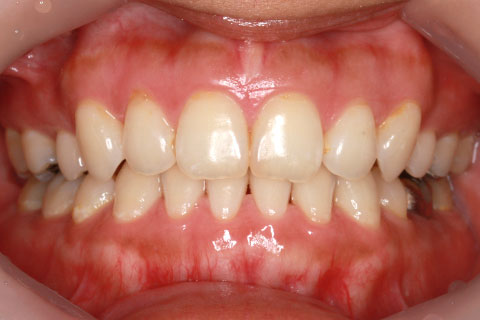

ハーフリンガル矯正3:上の歯のみ舌側矯正で治療(矯正期間24ヶ月)

治療前

治療中(開始直後)

治療中(開始半年後)

治療後

- 年齢・性別

- 25歳女性

- 治療期間

- 2年0ヶ月

- 抜歯

- 上下4番抜歯

- 治療費

- 110万円

- 治療内容

- 施術の副作用(リスク)

- 表側矯正と比較して、力学的な操作性が複雑なため、ボーイングエフェクトを起こしやすい。